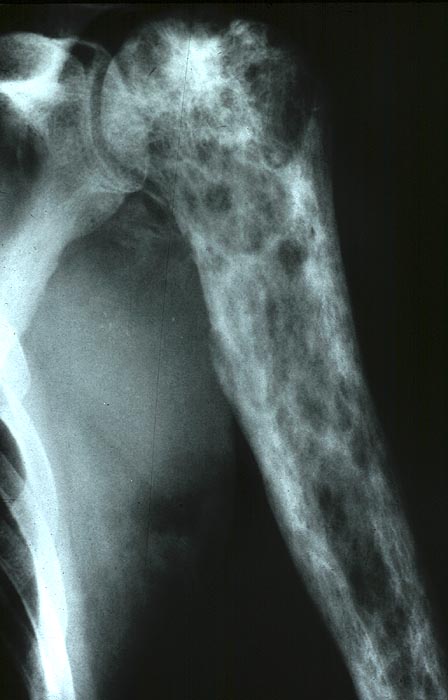

PathoPic ID 5039 - Chondrosarkom

Chondrosarkom

maligner Tumor

Knochen, Humerus

Knochen, Knorpel, Gelenke

Neben lytischen Veränderungen Ablagerung von fleckförmig verkalkter Knorpelmatrix.

Radiologie